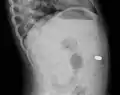

معرض صور